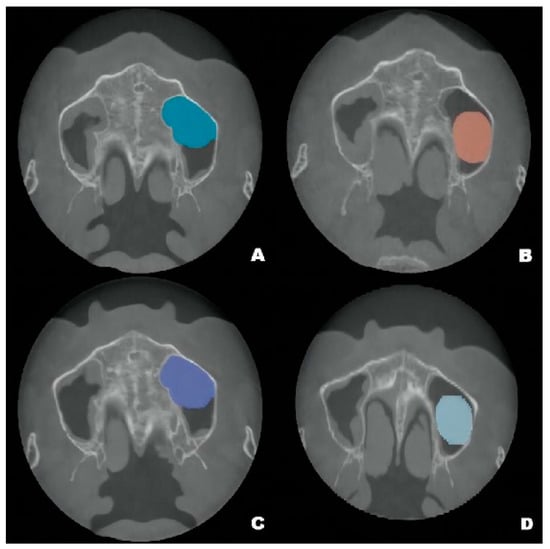

Figure 4.

Pseudocyst drift behavior: the pseudocyst had moved posterolaterally from the preoperative position (A) at 6 months after surgery (B), then returned to its original position at 12 months after surgery (C). At 22 months, the pseudocyst had remigrated to the posterolateral position (D).

Although the final crown restoration (second procedure) was planned for 6 months after the first procedure, it was delayed until 10 months because of an outbreak of COVID-19. A CBCT scan at the 6-month follow-up showed that the implants had been correctly placed in the augmented sinus, resulting in osseointegration without mobility (Figure 3B). CBCT scans at 12 months and 22 months showed stable bone levels around the implants (Figure 3C,D). The patient reported no discomfort or other complaints in relation to the implants or the maxillary sinus, and no fluid leakage was evident on the incision line during follow-up. However, a comparison of the preoperative CBCT scans with the postoperative scans conducted at 6, 12, and 22 months revealed pseudocyst drift in the left maxillary sinus (Figure 4). At 6 months after surgery, the pseudocyst had moved posterolaterally from the preoperative position near the anterior medial maxillary sinus, then returned to its original position at 12 months. However, it had remigrated to the posterolateral position at 22 months.

Pseudocyst drift may result from the following factors. First, the pseudocyst may not be completely immobile on the maxillary sinus floor. The pseudocyst may be entirely detached from the sinus floor, or it may be solely attached to the anterior portion of the sinus floor. In either situation, various forces, including implant insertion, airflow pressure from breathing, and postural changes during radiographic assessment could influence pseudocyst location. Second, considering the changes in volume, multiple pseudocysts may be present; the sizes of the pseudocysts may increase and decrease over time.